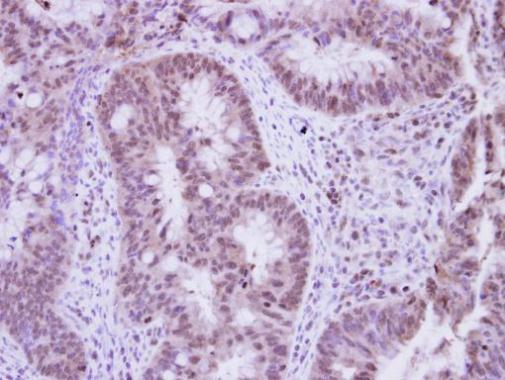

Immunohistochemical analysis of paraffin-embedded human colon carcinoma, using Vinexin(GTX115362) antibody at 1:250 dilution.

Antigen Retrieval: Trilogy™ (EDTA based, pH 8.0) buffer, 15min